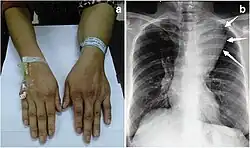

| Large mediastinal angiolipoma | |

Angiolipoma typically manifests as many, painful subcutaneous nodules (solitary in only one-third of patients), most commonly originating in the upper limbs (of which the forearm accounts for around two thirds), trunk, and lower limbs.[3][4] These lesions are well-defined, usually measuring less than 4 cm.[5]